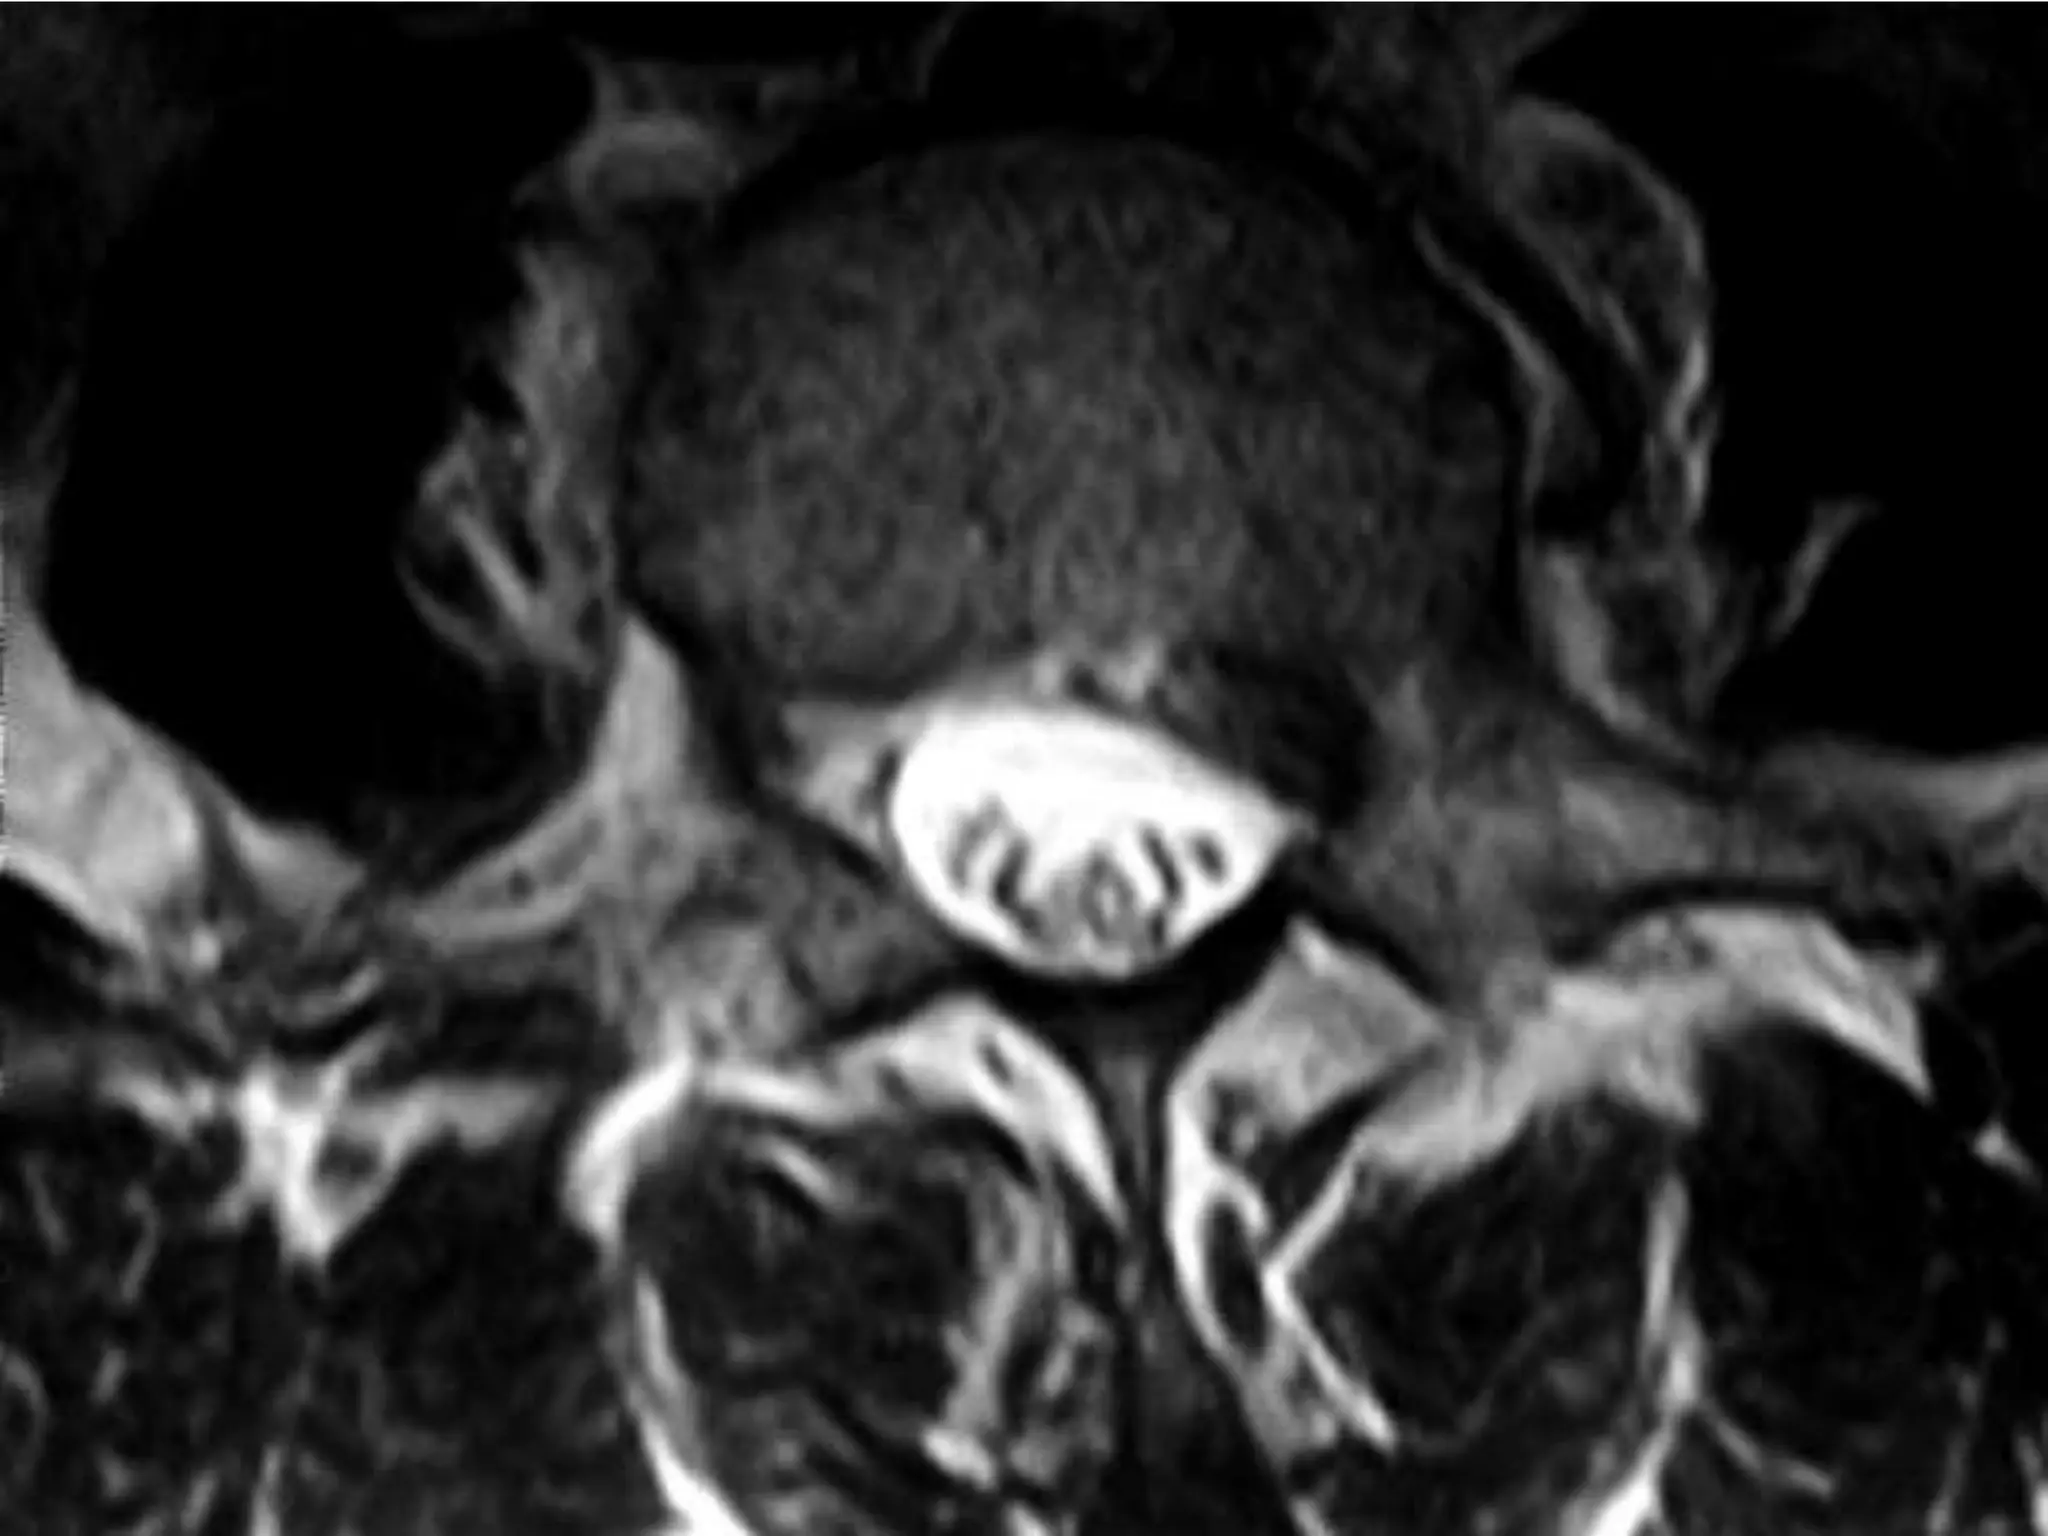

Dorsal Discs

Disc at D12 – L1